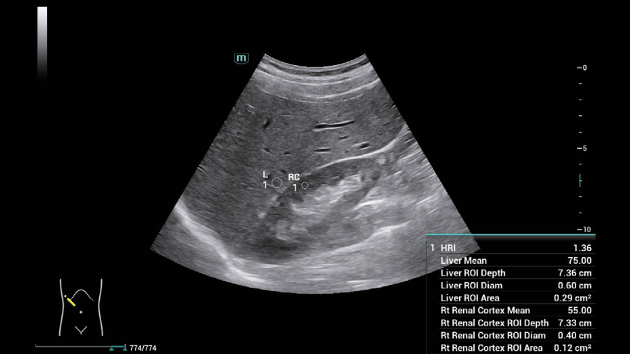

ZST+ ??? ???? ?? ???

ZST+ ???? ???? ??? ???? ??? ?????. ??? ???? ?? ? ???? ?? ??? ?? ??? ?????. ??? ??? ? ?? ??? ??? ???? ?????? ??? ???? ???? ??? ?? ?? ?? ?? ???? ?? ??? ?? ??? ?????.